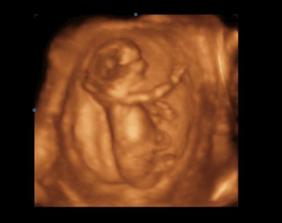

14.1.2010 3D ultrazvuk podľa PM presne 13tt+0 , na drobčeka sa bol pozrieť 1.krat aj tatinko, bolo to krásne 🙂 /////